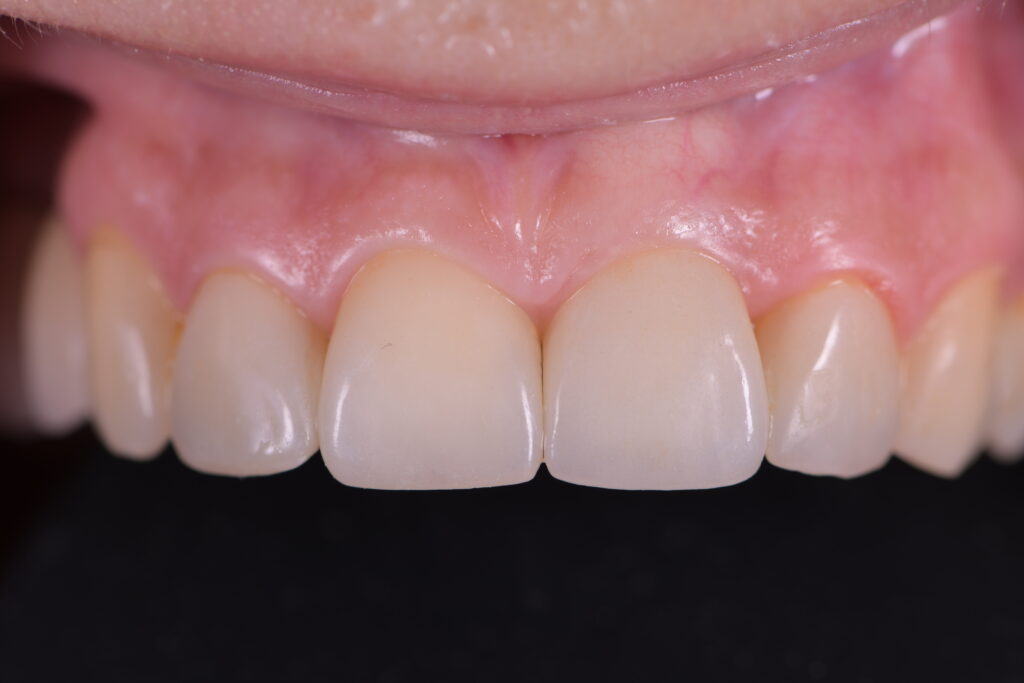

Fig. 6: Final situation with the screw-retained implant-supported restoration 21